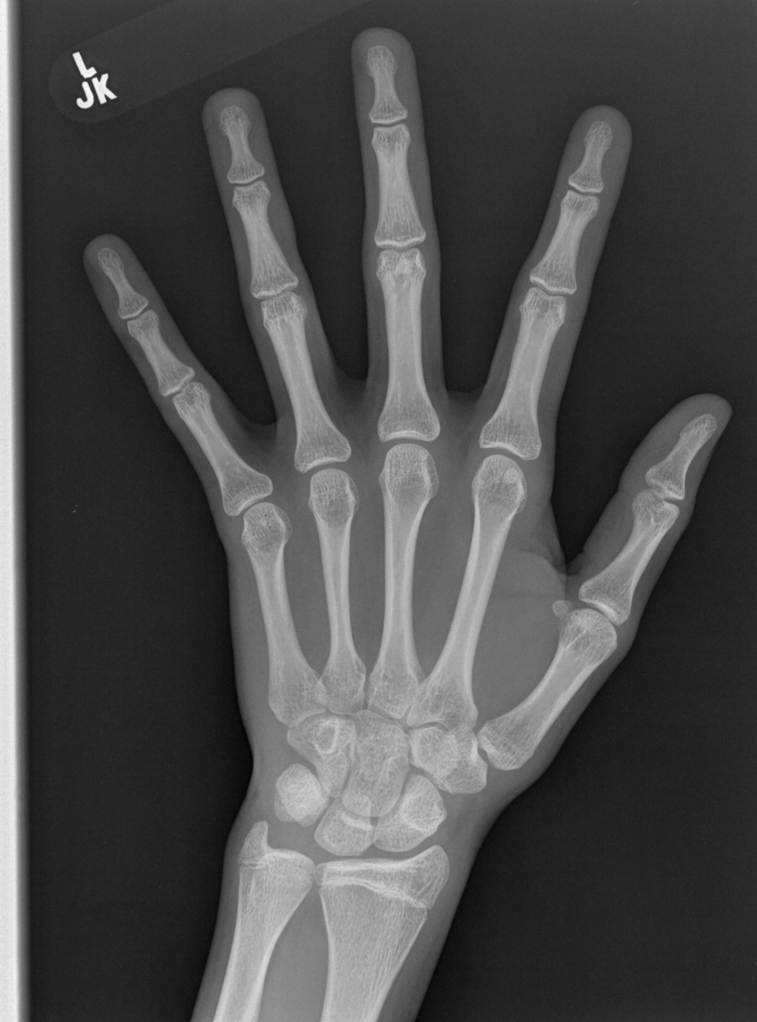

Refer to caption

(a) resolution 2044×1514204415142044\times 1514, run time 0.35s, α=1.34𝛼1.34\alpha=1.34

(b) resolution 2044×1514204415142044\times 1514, run time 0.35s, α=1.39𝛼1.39\alpha=1.39

(c) resolution 2044×1514204415142044\times 1514, run time 0.35s, α=1.63𝛼1.63\alpha=1.63

(d) resolution 2044×1514204415142044\times 1514, run time 0.35s, α=2.42𝛼2.42\alpha=2.42

(e) resolution 2044×1514204415142044\times 1514, run time 0.35s, α=2.31𝛼2.31\alpha=2.31

(f) resolution 2044×1514204415142044\times 1514, run time 0.35s, α=3.61𝛼3.61\alpha=3.61

(g) resolution 2044×1514204415142044\times 1514, run time 0.35s, α=3.02𝛼3.02\alpha=3.02

(h) resolution 2044×1514204415142044\times 1514, run time 0.35s, α=1.47𝛼1.47\alpha=1.47

(i) resolution 2044×1514204415142044\times 1514, run time 0.35s, α=2.11𝛼2.11\alpha=2.11

(j) resolution 2570×2040257020402570\times 2040, run time 0.58s, α=2.34𝛼2.34\alpha=2.34

Figure 10: From left to right in each panel: input X-ray images (left), our estimated soft tissue (middle) and estimated bone image (right). The resolution, running time of our algorithm and parameter α𝛼\alpha are provided. For these practical images, our method requires about half second to achieve the bone and soft tissue decomposition task in MATLAB language on a laptop. Higher performance can be achieved by C++ language on a better hardware.

In the third experiment, we applied our method on a hand X-ray image data set (RSNA), which contains more than 10,000 hand X-ray images. And the image has high resolution (usually larger than 1514×2044151420441514\times 2044). These images are collected from clinical applications. Therefore, we can apply our method on these practical images, showing the efficiency and effectiveness of our method on real high resolution images.

In each panel of Fig. 10, the input image (left) is decomposed into soft tissue (middle) and bone image (right) by our method. Although we only show the first ten images from the data set, the results for the rest images are similar.

The bone images have better image contrast since the parameter α1𝛼1\alpha\geq 1 is theoretically guaranteed. Such enhancement can also be directly told by radiologists. Such enhancement is good for bone diagnosis in practical applications.

Moreover, the running time of our method on such high resolution images is less than half second in the MATLAB language on a laptop. Therefore, it can achieve higher performance on a better hardware in real applications. If higher performance is required, our model can be solved by the parallel Laplace equation solver on a modern graphic process unit (GPU), which usually has thousands of cores.